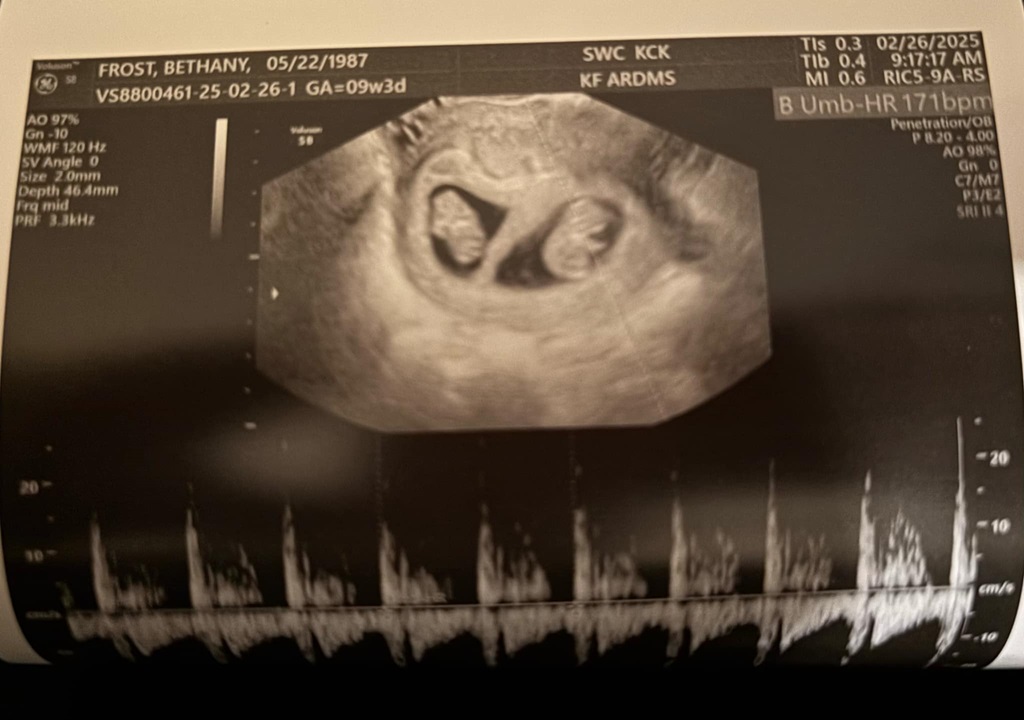

That’s right… twins. Not only did I defy the odds of getting pregnant at all, especially for my age. But I’m having twins. They’re called Di/Di twins. 2 separate eggs, so they each have their own little apartment separate from each other. Apparently this is great because there’s less risk for them to wrap cords around each other and so on. It also means we can end up with: boy/girl, boy/boy, girl/girl. Both are also an interesting anomaly according to the sono tech. Twins usually measure about a week off from each other. So one will measure 9 weeks, and the other 8 weeks. NOPE! Both are measuring 9 weeks 3 days. They both also currently have the same exact heartbeat of 171!! It was so cool to hear it too. Since it is Twins, I am 100% high risk now. We are doing a genetics test in a couple weeks, then another sono with the high risk doctor.

So yea! What a year! Meet the Frost Twins!!!